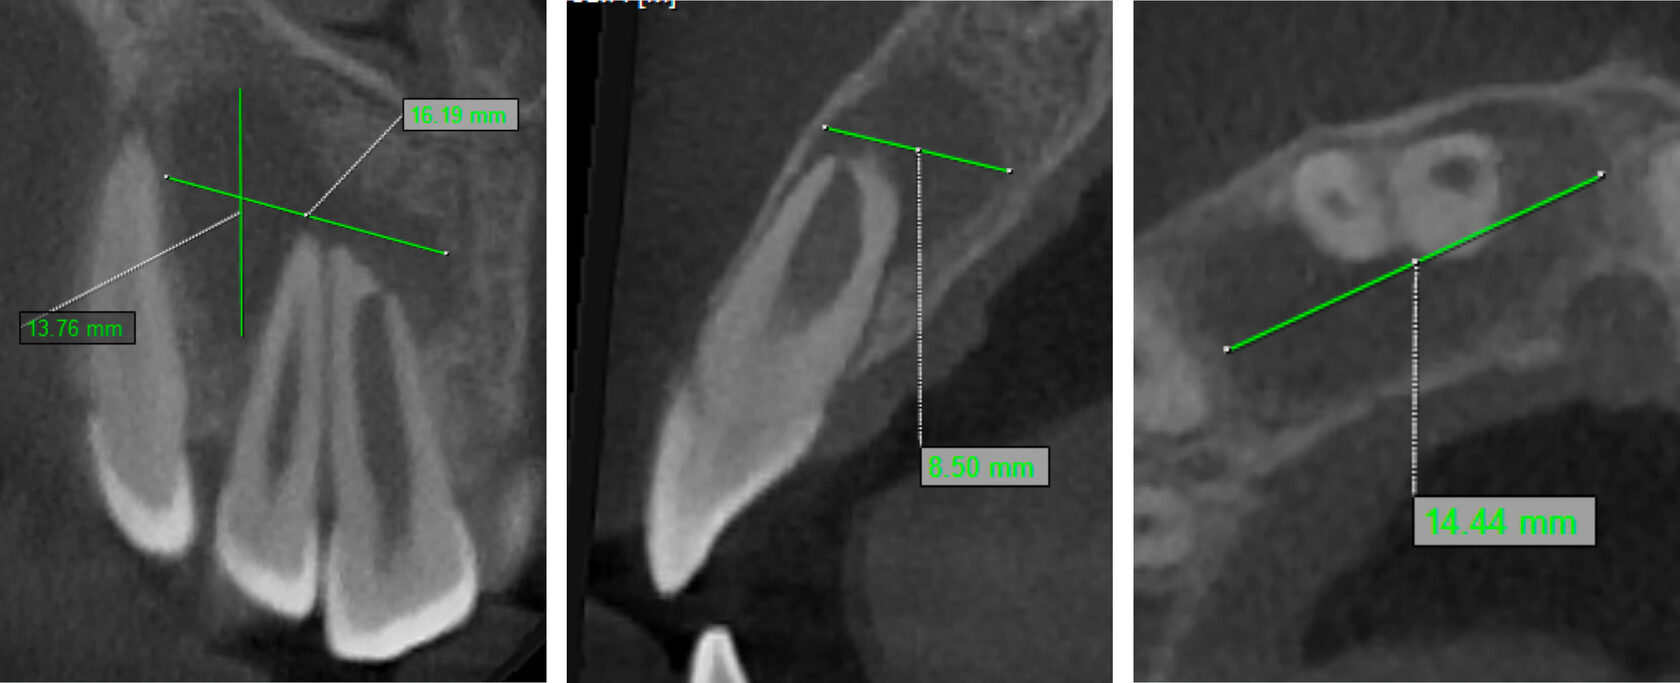

2. Tooth #11 was diagnosed as non-vital with apical periodontitis, presenting extensive periapical bone destruction radiographically. In contrast, tooth #12 responded normally to vitality tests, confirming pulp vitality. (Image 2,3,4)